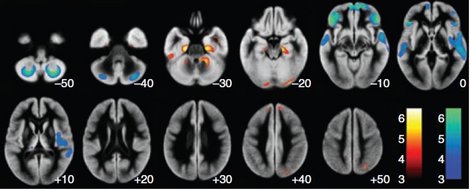

写真中: 研究用脳画像 写真下: NRW州アーヘンのデジタル・ハブ